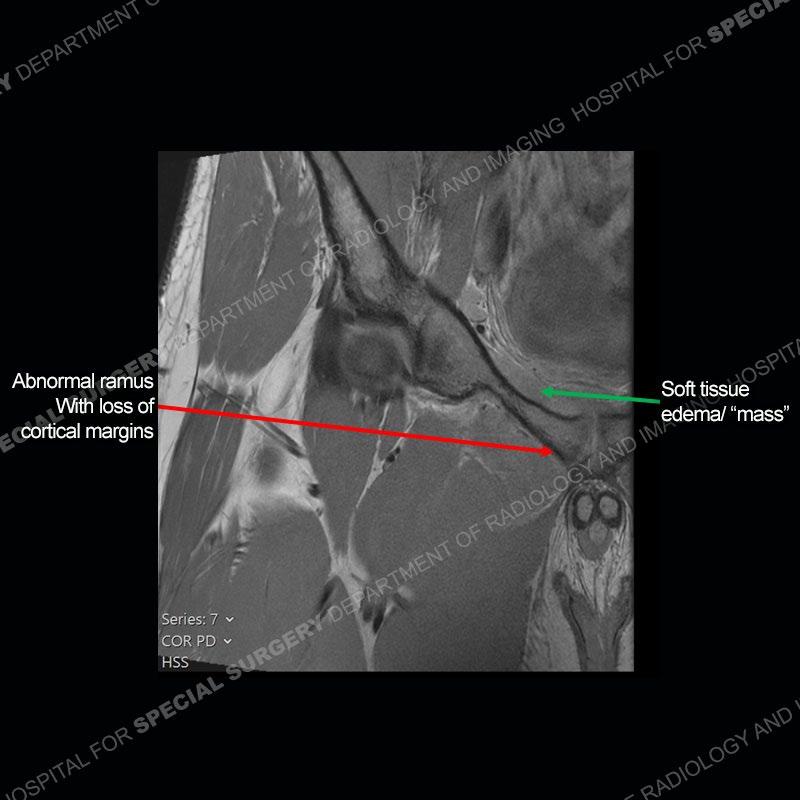

Radiographs did not demonstrate any clear abnormality. The MRI shows markedly abnormal signal of the right superior pubic ramus and abnormal signal/”mass” extending into the adjacent soft tissue. The inferior articular surface of the ramus showed what was thought to be bony destruction. CT examination shows a destructive process of the right superior pubic ramus.

Subsequent MRI in a very short time interval shows markedly increased abnormality of the ramus and increased edema and “mass” of the soft tissue. Post contrast imaging shows multiple, rim enhancing collections of the soft tissue and similar albeit less conspicuous enhancing collection of the ramus.

The repeat MRI, with the marked degree of increased abnormality of the bone and soft tissue shifted the diagnosis to a high degree towards infection. Even the most aggressive of neoplasms would not have that the degree of change in a 3-day time span. The CT study was shown before the repeat MRI but actually occurred just after the repeat MRI. It helped confirm the destructive process of the ramus and particularly the abnormal architecture along the inferior margin. The patient went on to have a CT guided aspiration of one of the soft tissue collections with 4cc of purulent fluid obtained. A surgical irrigation and debridement of the bone and soft tissue was performed. A PICC line was placed and the patient is currently undergoing IV antibiotic treatment with a possible repeat irrigation and debridement.